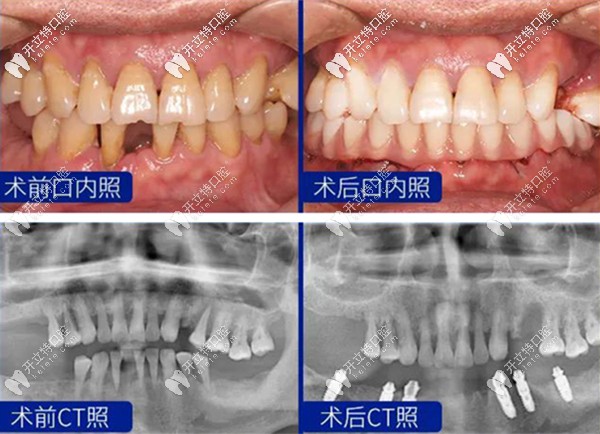

王旭醫(yī)生的半口種植牙案例效果圖